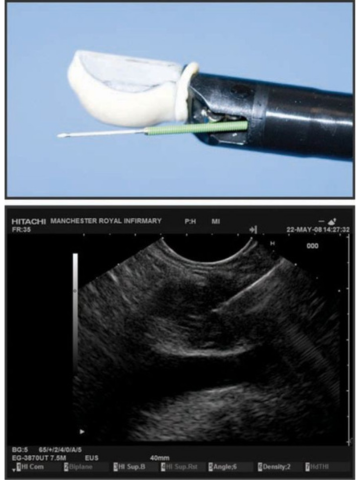

Існує два типи широко використовуваних ехоендоскопів, кожен з яких відрізняється своїми характеристиками. Радіальний ЕУЗД був першим, який був розроблений з забезпеченням 360-градусного огляду в площині, перпендикулярній до осцилографа, подібно до зображення комп’ютерної томографії (КТ) (мал. 2). Лінійне ехоендоскопічне ультразвукове дослідження забезпечує локалізоване косе зображення, паралельне ендоскопу, і дає змогу проводити терапевтичну діагностику ультразвуком (мал. 3). Також доступні високочастотні мінідатчики ЕУЗД, які можна пропускати через стандартний біопсійний канал ендоскопа у випадках, коли структури неможливо пройти за допомогою стандартного ендоскопа.